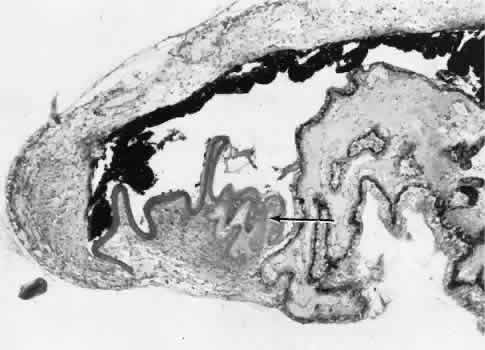

Fig. 31. A case of choroidal detachment. A. By fundus reflex, a large dome-shaped mass can be seen originating from the choroid. The differential diagnosis would include uveal malignant melanoma. In this case, the clinical findings were due to choroidal detachment from the sclera because of fluid accumulating in the suprachoroidal space following cataract surgery. B. The histologic section from another case of choroidal detachment illustrates the location (arrow) and extent of the detachment. In this case the detachment extends to the region of the ciliary body limited anteriorly by the attachment of the choroid to the scleral spur. The displacement of the ciliary body will result in apparent shallowing of the anterior chamber. (Hematoxylin-eosin stain; × 6.)